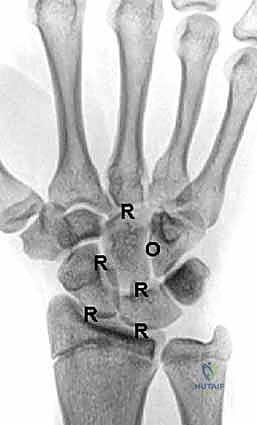

لفهم سبب تعقيد التهاب الرسغ وضرورة عملية التثبيت، يجب أن نلقي نظرة عميقة على التشريح المذهل لهذا المفصل. الرسغ ليس مفصلاً واحداً، بل هو مجموعة من المفاصل المتداخلة:

- عظم الكعبرة (Radius): العظم الرئيسي في الساعد الذي يحمل معظم وزن اليد.

- عظم الزند (Ulna): العظم الأصغر في الساعد، ويساهم في دوران المعصم.

- الصف الداني من عظام الرسغ (Proximal Row): يتكون من العظم الزورقي (Scaphoid)، الهلالي (Lunate)، والمثلثي (Triquetrum). هذا الصف هو الذي يتمفصل مباشرة مع عظم الكعبرة.

- الصف القاصي من عظام الرسغ (Distal Row): يتكون من العظم المربعي (Trapezium)، شبه المنحرف (Trapezoid)، ذو الرأس (Capitate)، والكلابي (Hamate). هذا الصف يتمفصل مع عظام المشط في اليد.

يُغطى كل سطح من هذه العظام بـ غضروف زجاجي (Hyaline Cartilage) أملس يسمح بانزلاق العظام فوق بعضها البعض دون احتكاك. عندما يُدمر هذا الغضروف (بسبب العمر، المرض، أو الإصابة)، تصبح الأسطح العظمية خشنة، وتنمو نتوءات عظمية (Osteophytes)، وتتمزق الأربطة، مما يؤدي إلى انهيار هيكلية الرسغ بالكامل.

- التصوير بالأشعة السينية (X-rays): الأداة الأساسية لتقييم تضيق المسافة المفصلية (دليل على فقدان الغضروف)، وجود نتوءات عظمية، وتحديد مدى الانهيار في عظام الرسغ.